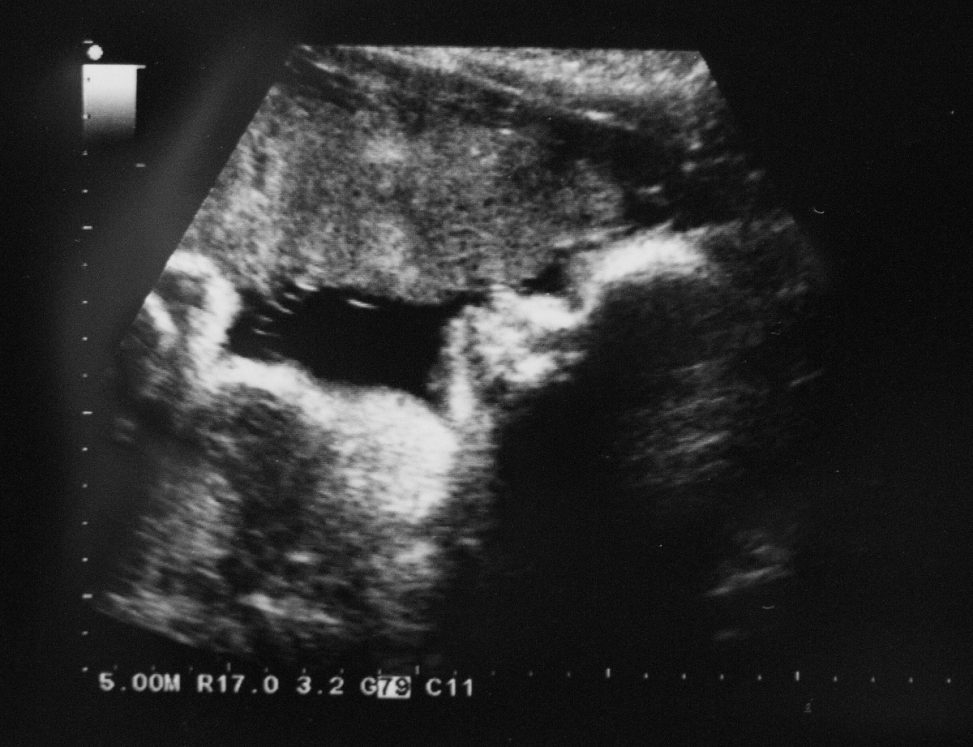

We had our final scan today. What an amazing experience they are.

Today we could clearly make out little baby ‘breathing’. Ok, so there wasn’t any air but baby was busy practicing to strengthen the muscles, that little chest moving in and out quite clearly on screen.

We are really happy, baby is growing well. Perfectly average on all measurements – I don’t think I have said it often, but sometimes it’s fantastic to be spot on average.